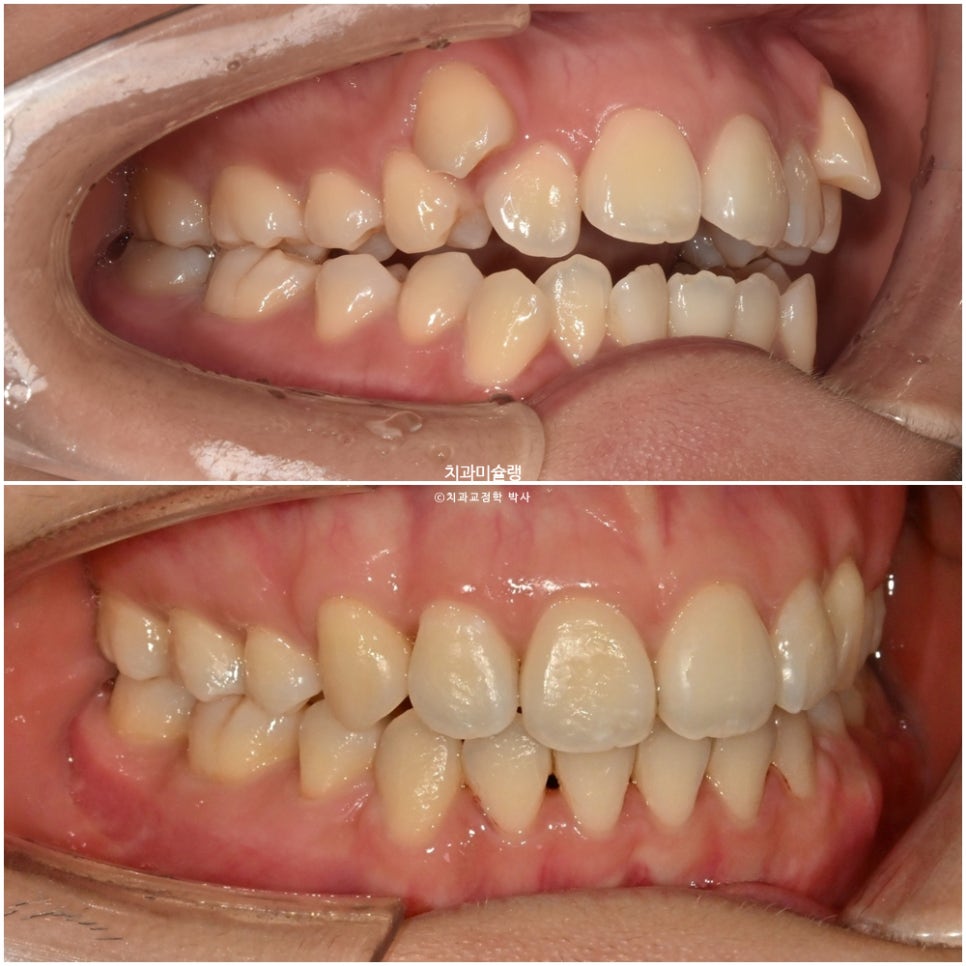

어금니 교합관계는 2급 입니다.

치료 중 워낙 위치가 높았던 송곳니가 잘 맞지 않아 고무줄을 끼면서 진행했고

중심선은 잘 맞으며 송곳니는 제자리로 잘 내려왔죠. 개방교합도 완벽히 개선되었습니다.

어금니 교합은 이미 좋습니다.

어금니 교합은 좋으며 1급 교합관계를 보입니다.

치료 결과 비교

이제 전후비교 보겠습니다.

송곳니 덧니 때문에 윗입술 양측이 들려있던 부분이 개선되었습니다.

아랫입술은 소량 뒤로 들어갔고 윗입술은 거의 처음 그대로 유지되었습니다.